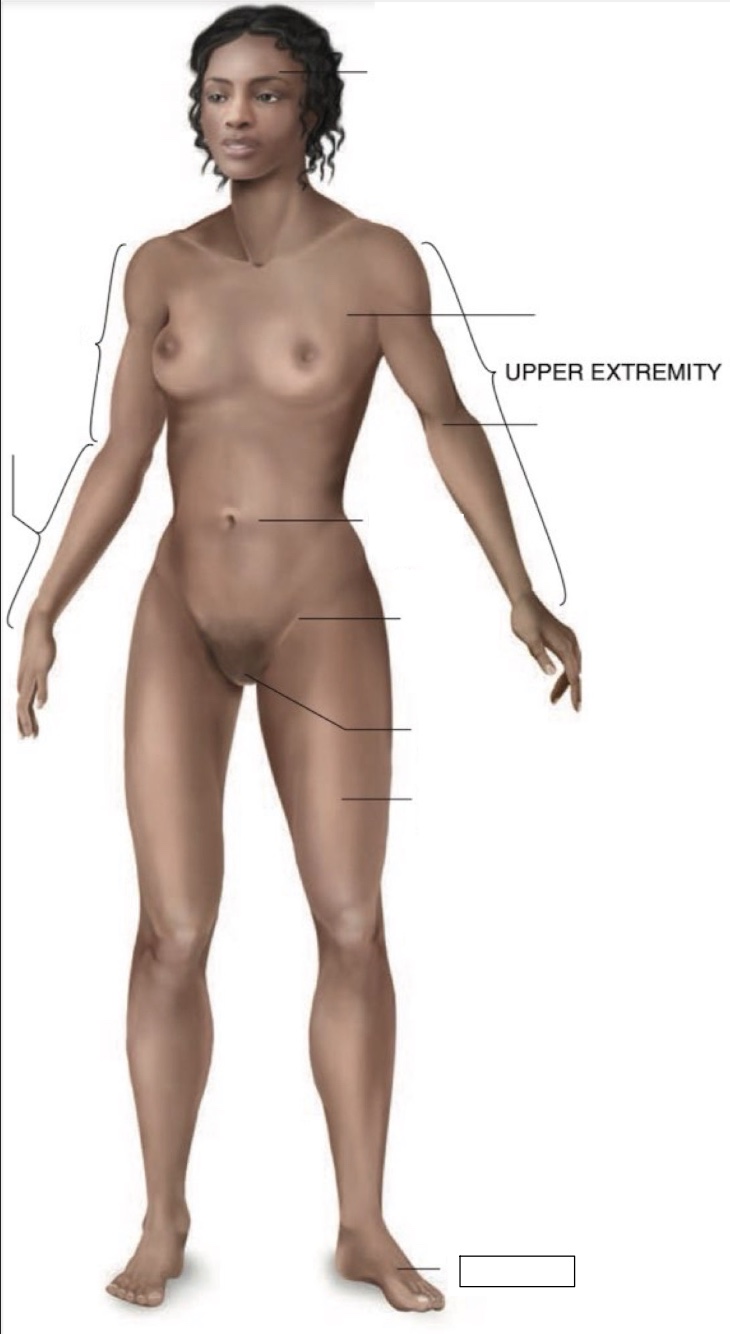

Cranial region

thoracic region

umbilical region

inguinal region

genital region

femoral region

dorsum of foot

arm

forearm

cubital region

Torso

Inferior

Midline